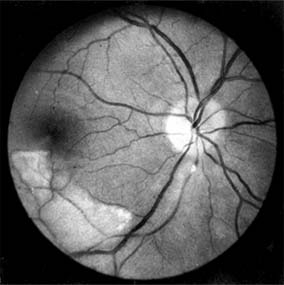

Figure 15-10

Figure 15-10: Accelerated hypertension. Fluorescein angiogram in a young man showing arteriolar constriction, dilation of capillaries with microaneurysms, and areas of closure. Marked disk edema is present.

In contrast, elderly patients with arteriosclerotic vessels are unable to respond in this manner, and their vessels are thus protected by the arteriosclerosis. It is for this reason that elderly patients seldom exhibit florid hypertensive retinopathy (Figure 15-11).

Figure 15-11

Figure 15-11: Accelerated hypertension. Fluorescein angiogram in an elderly wom.an showing marked arteriolar constriction and irregularity but few signs of florid retinopathy.

Fluorescein angiography has made possible accurate documentation of these microcirculatory changes. In young patients with hypertension, arteriolar attenuation and occlusion are seen, and capillary nonperfusion can be verified in relation to a cotton-wool spot, which is surrounded by abnormal dilated capillaries and microaneurysms with increased permeability on fluorescein angiography.

Resolution of the cotton-wool spots and the arteriolar changes occurs with successful hypotensive therapy. In elderly patients, the underlying arteriosclerotic changes are irreversible.